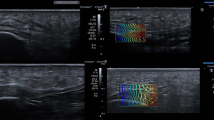

Strain elastography enables us to evaluate non-invasively the mechanical properties of biologic tissues, specifically tissue stiffness, by assessing the displacement of soft tissue structures after external compression [6]. It is increasingly used in musculoskeletal settings, already having an established role in lateral epicondylitis and Achilles tendinopathy [4]. Previous studies have shown that it might be used to highlight the softer appearance of the PF in plantar fasciitis, increasing the diagnostic performance of B-mode ultrasound and being supportive in doubtful cases with inconclusive ultrasound findings [7]. Some of the drawbacks of this technique, including the limited reproducibility and the qualitative nature of data, have led to the introduction of shear-wave elastography (SWE) as a quantitative and more objective tool to estimate soft tissues’ stiffness by using an acoustic radiation force pulse sequence to produce shear waves that propagate perpendicularly from the transducer with transient structures displacements [6]. Although SWE was investigated first in other districts (i.e. breast imaging), several research lines have been carried out to understand the actual role and additional value of SWE in musculoskeletal imaging. As a matter of fact, some interesting papers have been published about the use of SWE to evaluate the PF over the last few years.

Over the last few years, sonoelastography has been increasingly used as an imaging tool able to help in evaluating PF status and composition from both a quantitative and qualitative point of view, in addition to the conventional B-mode ultrasound imaging [23]. Two sonoelastography methods are commonly used in musculoskeletal research and clinical practice: strain elastography, in which a mechanical force compresses the tissues axially, and SWE, in which compressive acoustic waves dynamically provide local stress in the soft tissues [24]. Strain elastography enables one to assess the deformation of the soft tissues along the propagation axis of the beam through the analysis of the RF signal along each line of scanning. The resulting colour elastogram that is generated is overlaid on the B-mode greyscale image, providing the operator with qualitative information about the tissue’s elasticity. The stiffness of PF may therefore be evaluated only qualitatively, although pseudo-quantitative information can be obtained by calculating strain ratios, which can be used to compare the PF strain with that of closing healthy tissue.

SWE allows a quantitative and reproducible approach for evaluating PF stiffness, being less operator-dependent than SES [25]. A focused acoustic radiation force is delivered from a linear US probe to induce shear waves throughout the soft tissues. These shear waves propagate perpendicularly at a slower velocity than the US beam, resulting in particle displacements that can be calculated using a speckle tracking algorithm. Tissue displacement maps are used to measure SWE velocity, expressed in meters per second. The distribution of shear wave velocities at each pixel is directly related to the shear modulus G (ratio of stress to strain), which is calculated by a simple mathematical equation and expresses the tissue stiffness and elasticity in units of pressure, usually kilopascals. In contrast to strain elastography, SWE allows quantitative measurements from any portion of the investigated PF within the colour elastogram due to the sequencing of particle displacements made possible by ultrafast analysis [23]. According to published studies on plantar fasciitis, SWE seems to be able to identify those degenerative changes that involve the PF, including collagen breakdown and disorientation, matrix degradation, increased mucoid content, and angiofibroblastic hyperplasia, which lead to the softer appearance of the PF in SWE [1]. It is true that strain elastography may provide an immediate assessment of PF stiffness, but SWE is more reliable and less operator-dependent, providing “numbers” that might be used in clinical practice to detect PF changes due to plantar fasciitis and to identify any response to treatment.